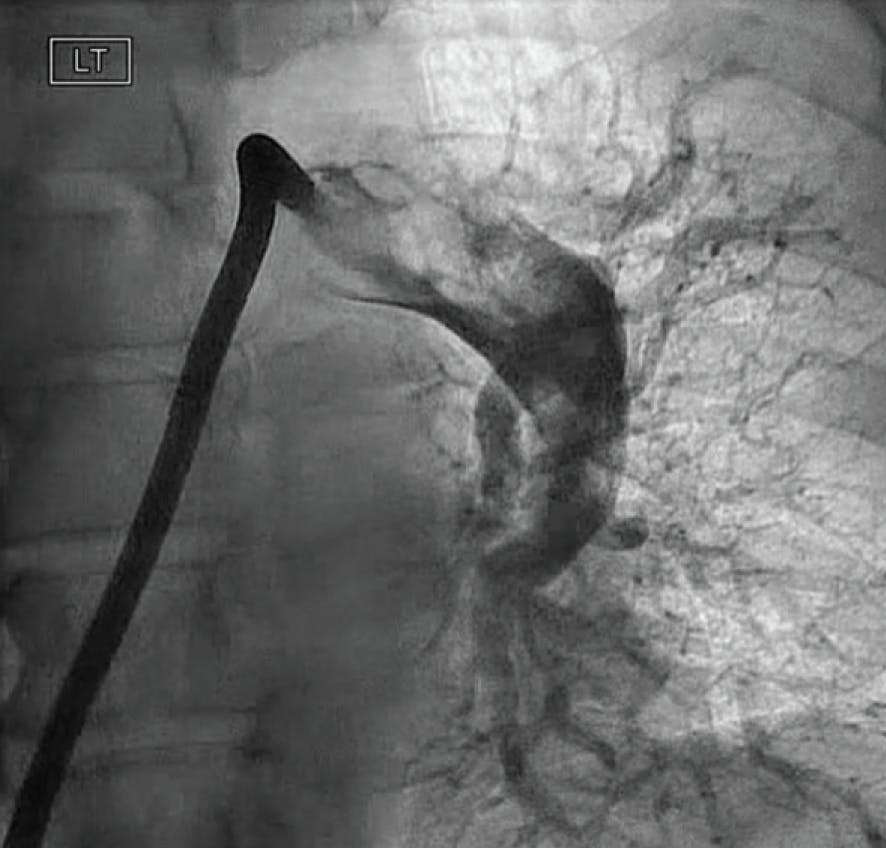

The patient was placed supine on the angiographic table with bilateral groins prepped and draped in sterile fashion. Access was obtained in the right common femoral vein utilizing real-time ultrasound and fluoroscopic guidance with a micropuncture kit with subsequent placement of a 7-F sheath. Over an Amplatz Super Stiff 0.035-inch guidewire (Boston Scientific Corporation), the venotomy was dilated and a 16-F Gore DrySeal sheath (Gore & Associates) was inserted. A 7-F balloon-tipped PA catheter was advanced under fluoroscopic guidance into the right atrium, right ventricle (RV), and left PA, at which time pressures were obtained and cardiac output/index was calculated. Pulmonary angiography of the left PA was performed under digital subtraction angiography, demonstrating large central thrombus occluding the left upper lobe and near occlusive in the left lower lobe.

Figure 1. Preprocedural angiogram of the left PA.